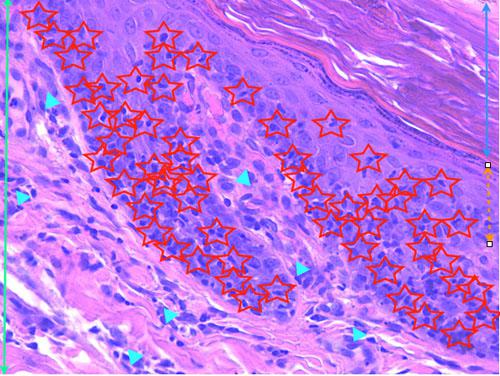

Photo 14 (Hémalun-Eosine X400): présence d’un infiltrat d’interface lymphocytaire

qui migre dans les couches les plus basales de l’épiderme. Le derme présente également un infiltrat périvasculaire.

Légendes de la Photo 14 :

- Double flèche bleue : couche cornée orthokératosique de l’épiderme

- Double flèche orange pointillée : épiderme (portion non kératinisée)

- Double flèche verte : derme

- Étoiles rouges : infiltrat lymphocytaire dans les couches les plus basales de l’épiderme (ici au sein de deux crêtes épidermiques)

- Triangles turquoises : infiltrat dermique mononucléé périvasculaire